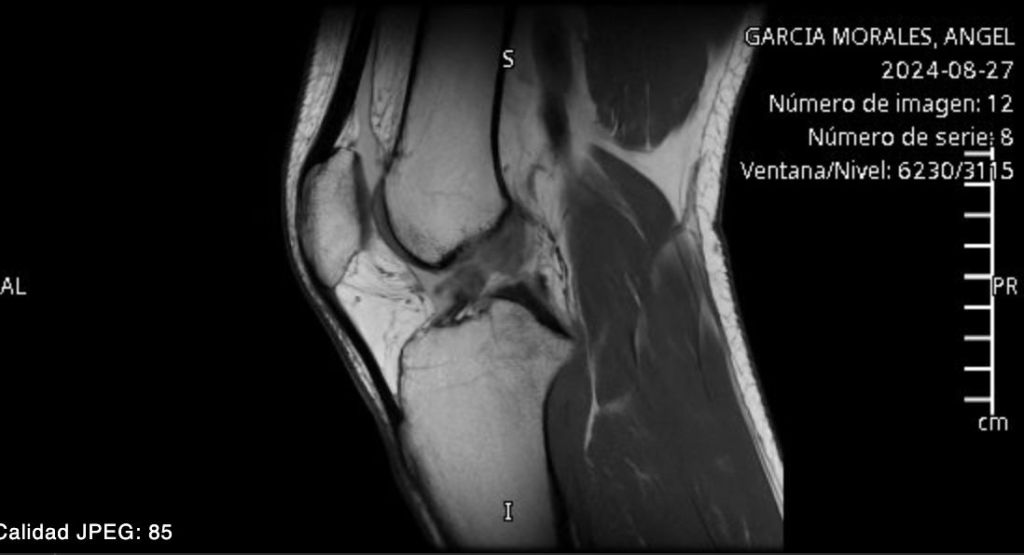

La Resonancia

28 de agosto. Xoco, Ciudad de México. Después de los 10 días de medicamentos, precauciones, analgésicos y dudas por fin se llegó el día de la resonancia magnética. ¿Quién diría que en ciertas clínicas las citas para el resonador las dan en plena madrugada?… a las 2:40 a.m. del día… Listen ⇢